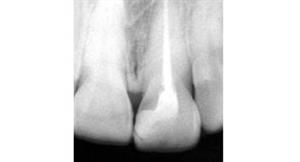

Root Canal Treatment

Before

After

A root canal procedure (endodontic treatment) is often required to save an infected tooth. Bacteria can enter a tooth through a cavity or a damaged filling. When this happens, the tooth can become abscessed, meaning the pulp inside the tooth becomes infected. An abscessed tooth can be quite painful and cause swelling in the surrounding gum tissues. If left untreated, it can cause several oral health problems. A root canal procedure removes the infected pulp and any other infected tissues within the tooth.